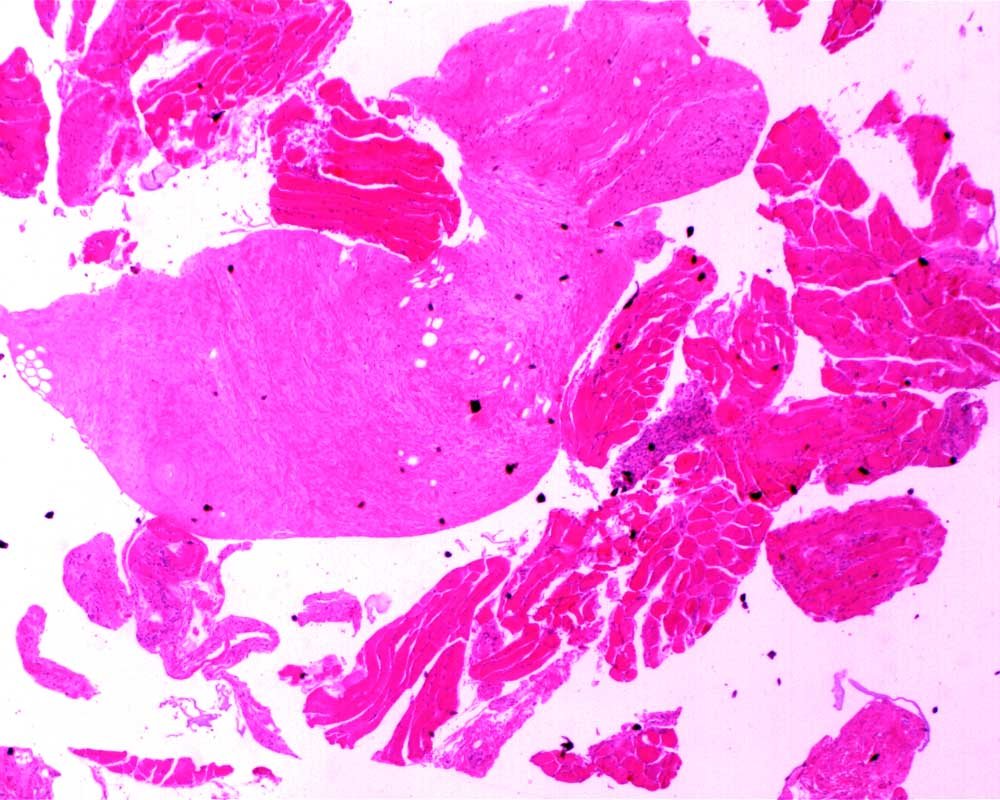

Case: ThighMass2

Final Diagnosis: